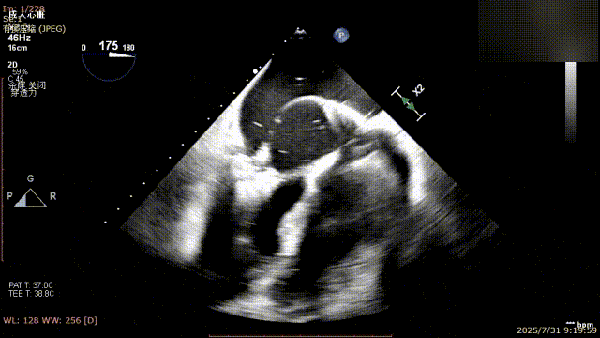

术前完善经食管超声评估,提示该患者双房大,二尖瓣重度反流4+伴后叶脱垂、后叶部分腱索断裂。根据评估结果,心脏大血管外科王安彪主任团队制定了周密的手术方案:植入一枚夹合器,钳夹P1区反流最大处,尽可能夹持全部后叶脱垂瓣叶组织,后续根据术中实时残余分流和跨瓣压差等指标,并依据实时超声监测调整治疗策略。

三维评估;二尖瓣P1脱垂偏心性返流

术前影像